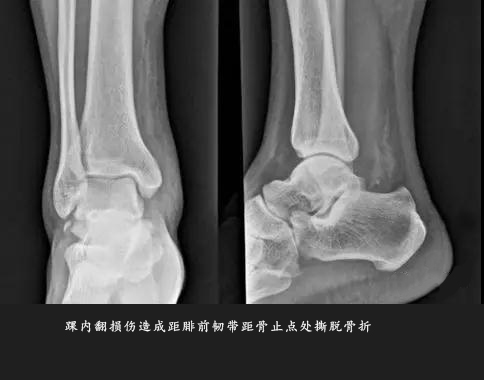

各类型撕脱骨折由于撕脱骨块较小或被重叠往往出现 X 表现的假阴性,另外由于患者不重视,未摄片检查以及采取不正当的处理措施,均容易遗漏撕脱骨折及韧带损伤的诊断。